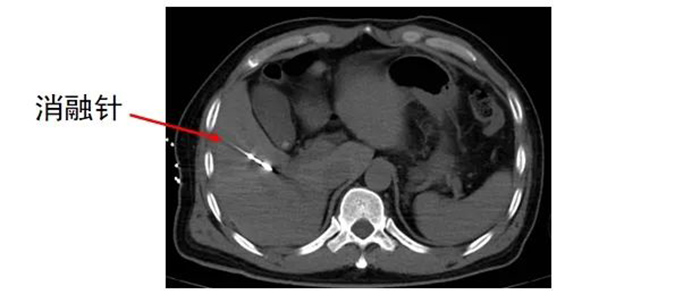

经多学科讨论,齐先生适合转化治疗,首先利用消融的方法解决肝内转移瘤,同时根据病理科基因检测结果进行全身系统治疗,待转化治疗成功,肿瘤缩小、降期后,吻合口复发区域再进行手术切除。 肿瘤科、麻醉手术科 及放射影像科协同合作 为齐先生进行 经皮肝恶性肿瘤微波消融术

齐先生病灶临近大血管、重要脏器。91club 专家团队在CT引导下精准定位,经皮穿刺将微波消融针准确置入齐先生肝脏肿瘤部位,然后利用微波能量,使肿瘤组织内的水分子快速振动、摩擦产生热量,从而使局部温度迅速升高,让肿瘤细胞凝固性坏死。整个手术过程顺利,避免了严重并发症发生。

准确插入到病灶内,并避开了门静脉右支及胆,避免了出血、损伤胆囊等并发症。